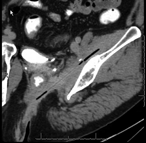

Thinking outside the rectum: a unique approach to the retrieval of gluteal foreign bodies

Sarah Blue and Melissa Najarian

Journal of Surgical Case Reports, Volume 2018, Issue 6, June 2018, rjy092, https://doi.org/10.1093/jscr/rjy092